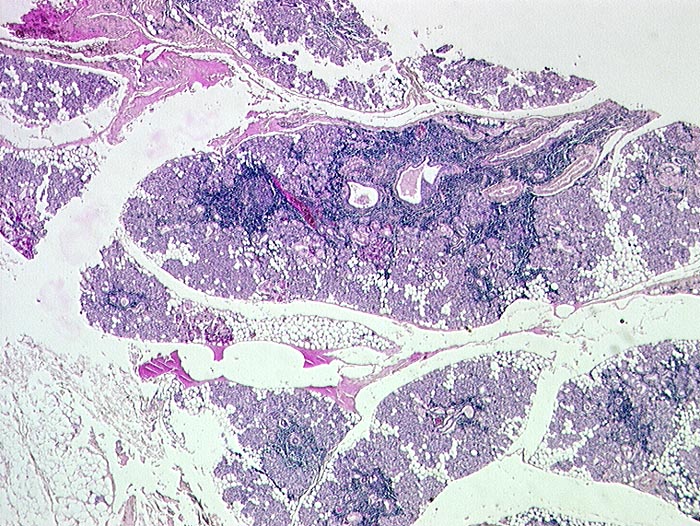

Das Zellbild ist je nach Stadium mehr oder weniger zellreich und zusammengesetzt aus Lymphozyten, Myoepithelien und selten Azinuszellen. Ein lymphozytäres Zellbild ist in Kombination mit dem typischen klinischen Bild (Keratokonjunktivitis sicca, Xerostomie, rheumatische Erkrankung) für die Sicherung der Diagnose ausreichend. Auf die Lippenbiopsie kann in diesem Fall verzichtet werden.